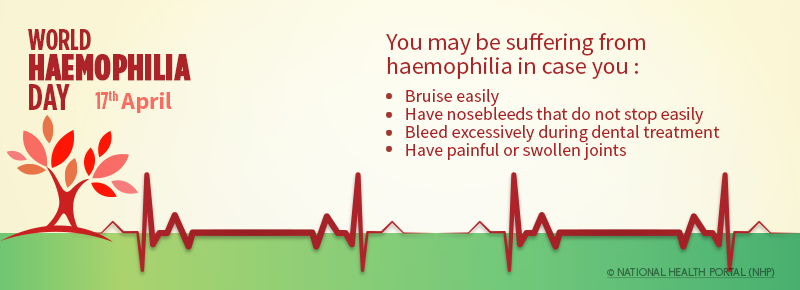

- Blood defects and diseases (e.g. leukemia, sickle cell anaemia etc.)